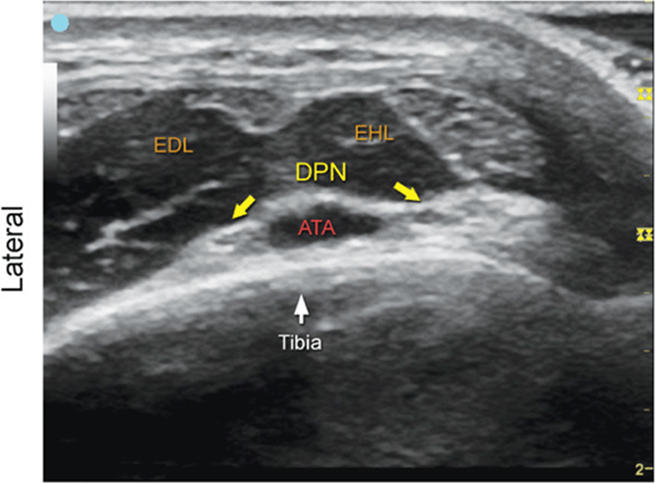

Peroneal Nerve, Deep and Superficial Branches

FIGURE 7.57.1A Ultrasound transducer position to image the peroneal nerve, deep and superficial branches.

FIGURE 7.57.1B Ultrasound image of the peroneal nerve, deep and superficial branches.

FIGURE 7.57.1C Labeled ultrasound image of the peroneal nerve, deep and superficial branches.

FIGURE 7.57.1D Labeled cross-sectional anatomy of the peroneal nerve, deep and superficial branches.

Abbreviations: PBM, Peroneus Brevis Muscle; EDL, Extensor Digitorum Longus; SPN, Superficial Peroneal Nerve; DPN, Deep Peroneal Nerve; ATA, Anterior Tibial Artery.